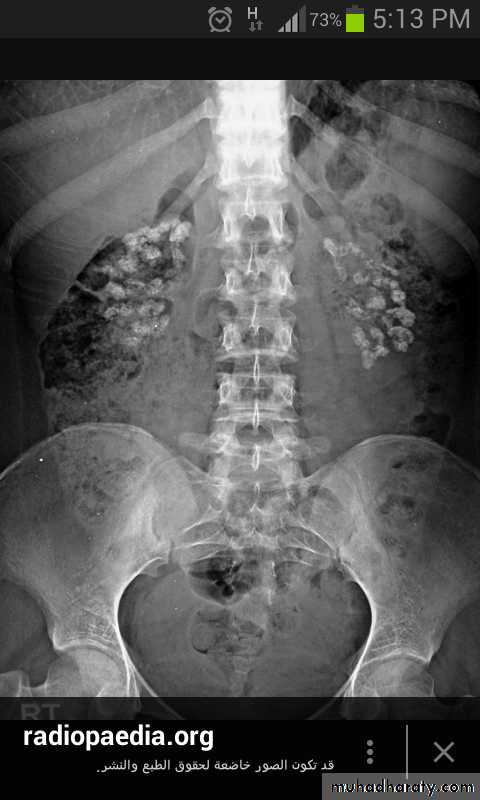

Nephrocalcinosis

Soft tissue calcification, vessels walls, hands and cornea

Investigations

Hypercalcemia

Hypercalciuria

Hypophosphatemia,

Raised PTH (fasting)

Normal renal function tests

Localization of the adenoma

Ultrasound

Neck MRI

99m Tc-sestamibi scintigraphy